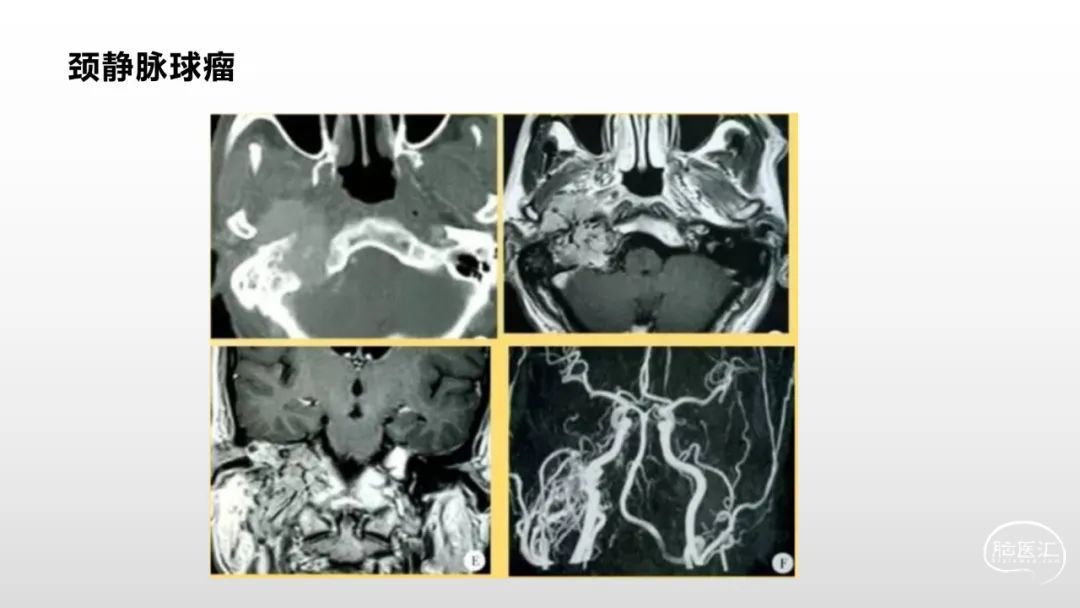

颅脑影像诊断基础知识讲座:脑膜病变